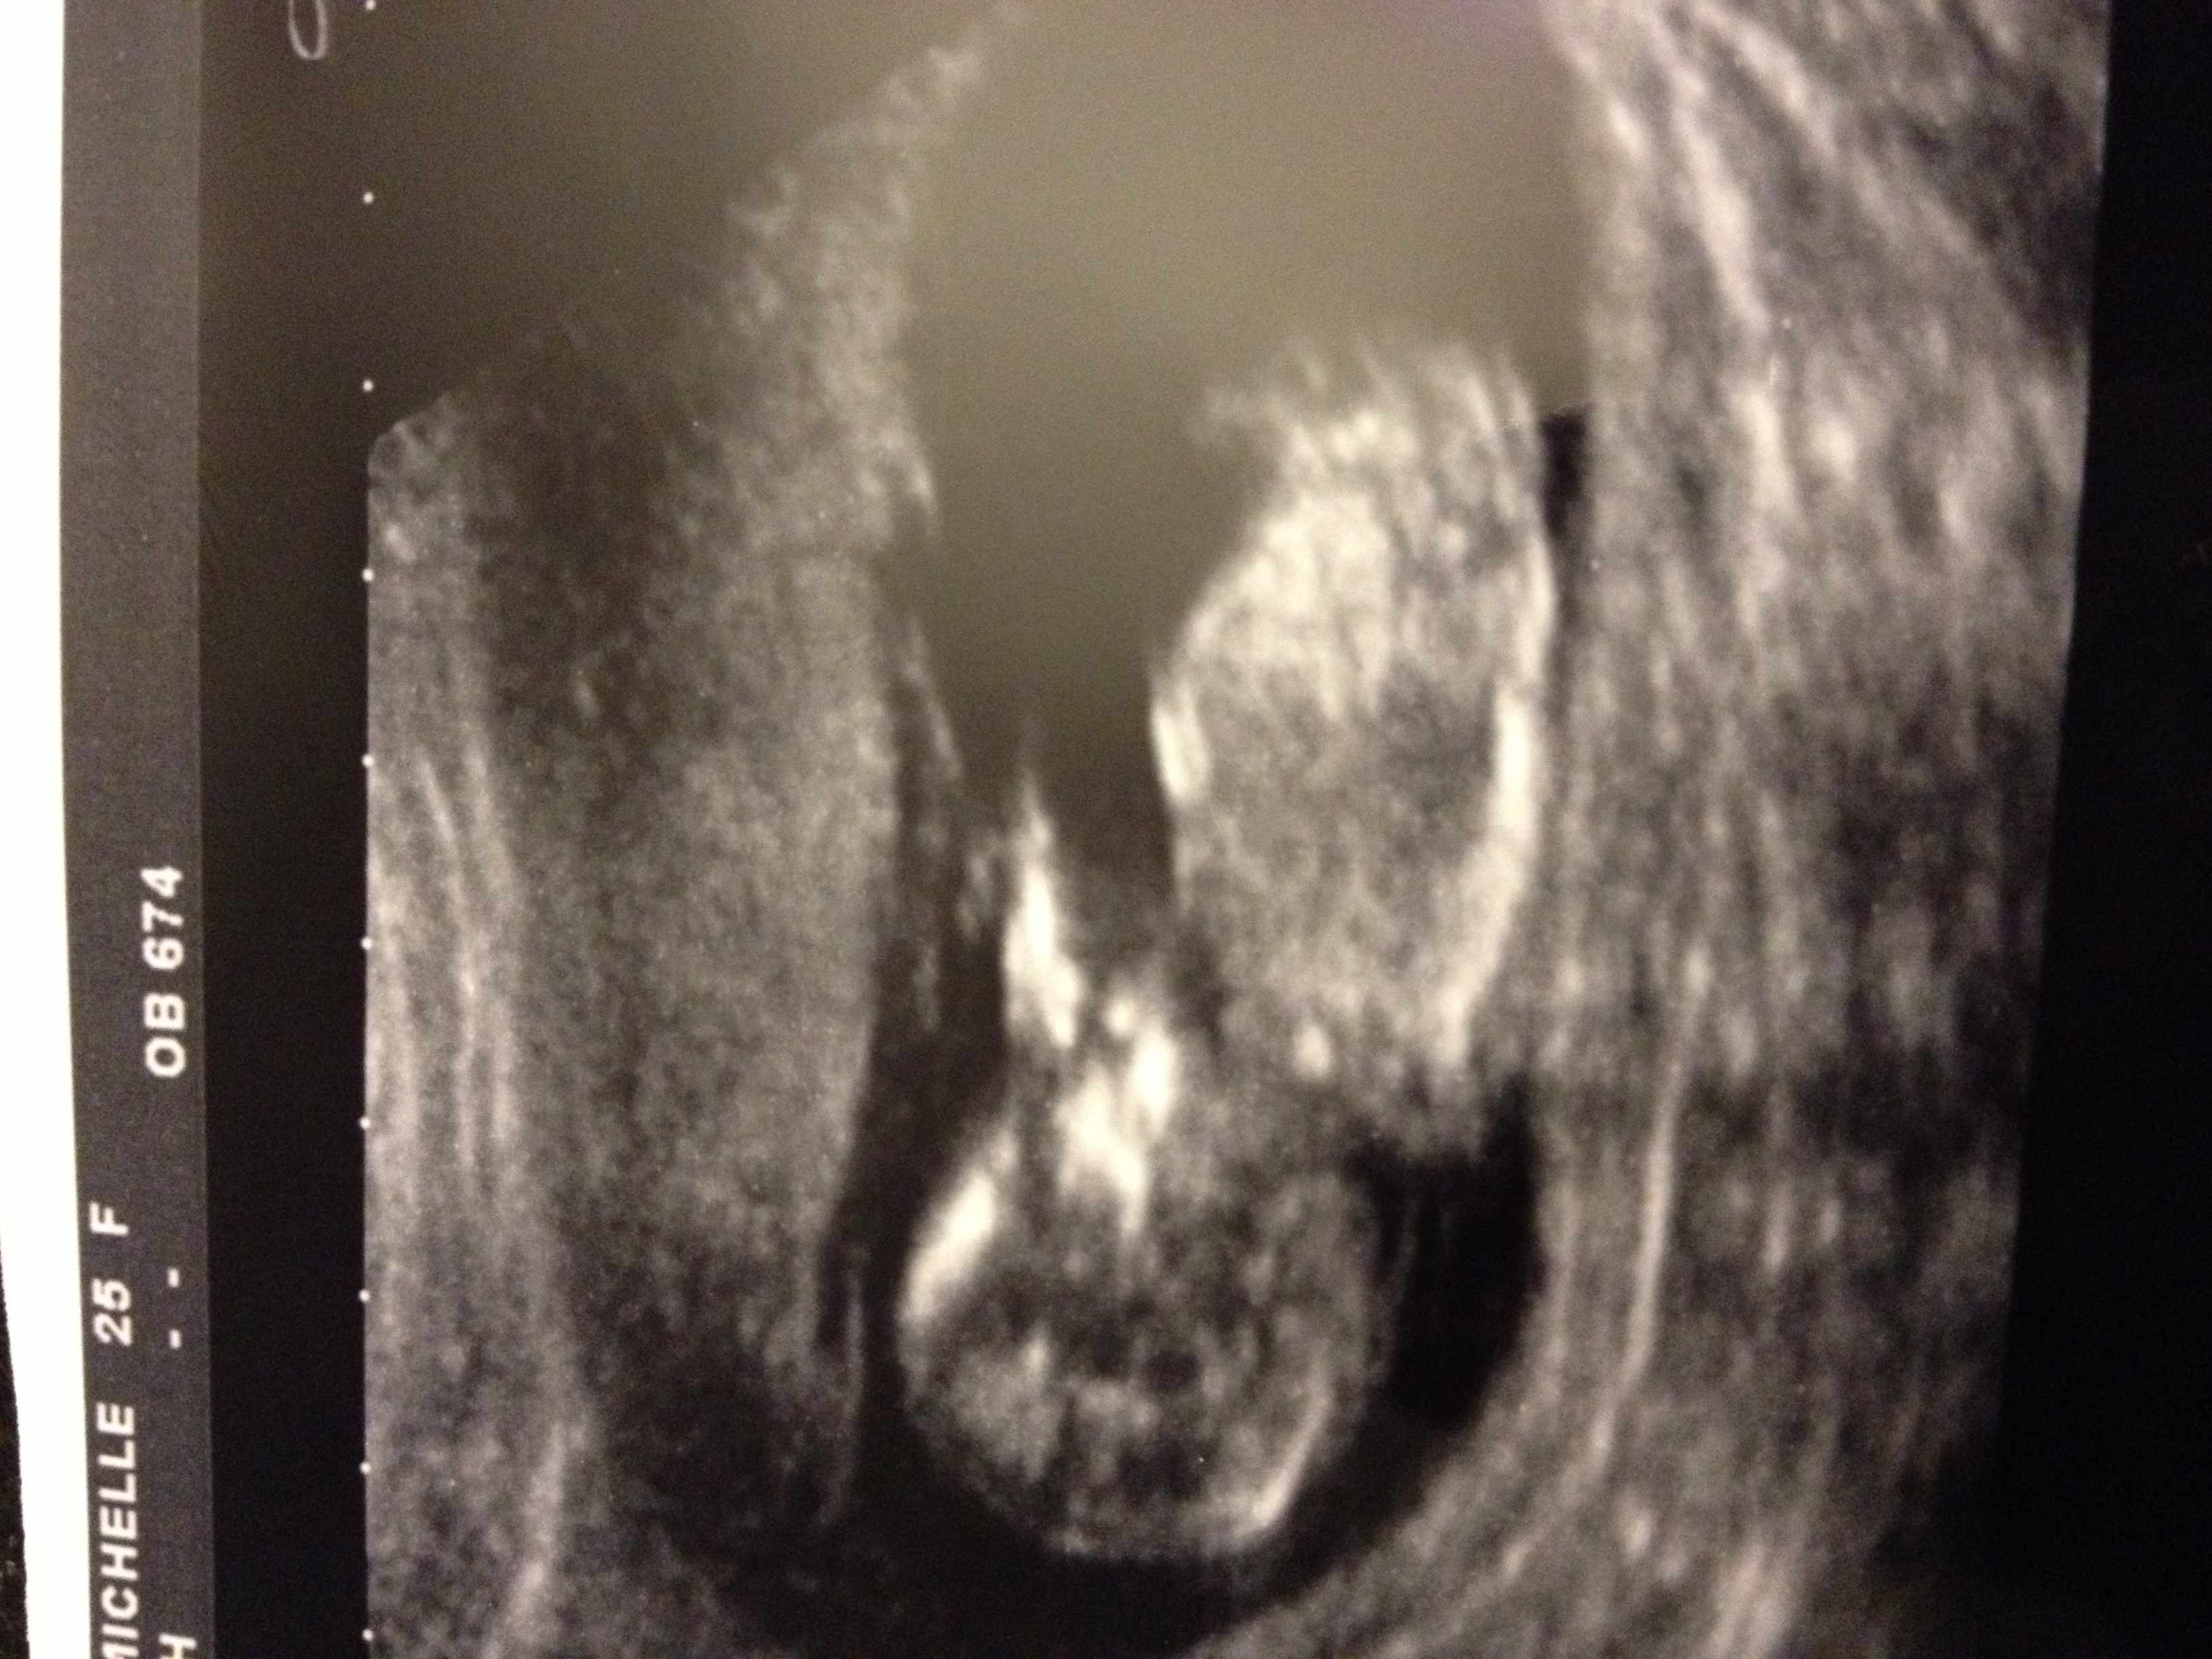

Attachment 9308Hey guys anyone fancy taking a guess at gender either nub or skill theory thank u very much in advance

Boy :HH:

Im not sure if I see a nub sorry x